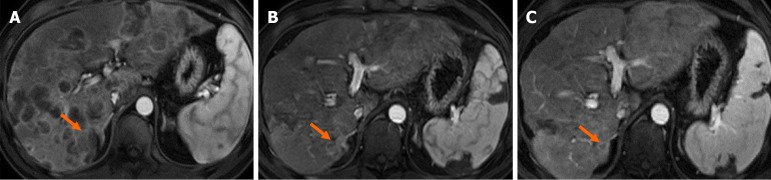

Case summary: A 45-year-old male presented with jaundice in December 2022. Initial investigations revealed a pancreatic head mass and liver metastases; a liver biopsy confirmed moderately differentiated adenocarcinoma. The patient received multimodal therapies, including gemcitabine, albumin-bound paclitaxel, nimotuzumab, and proton radiotherapy, which initially resulted in significant shrinkage of the pancreatic lesion and a reduction in liver metastases. However, the disease eventually progressed, prompting further evaluation at our MTB clinic. Genetic testing revealed a homologous recombination deficiency (HRD) score of 58 (HRD-positive) and a pathogenic BRCA2 mutation (p.T3033fs), suggesting sensitivity to PARP inhibitors and platinum-based therapies. Based on these findings, the patient was administered olaparib, which, combined with immunotherapy (tislelizumab, atezolizumab) and hepatic arterial infusion chemotherapy (5-fluorouracil + leucovorin + oxaliplatin regimen), led to further stabilization and partial reduction of liver metastases. This case underscores the positive role of the MTB model in interpreting genetic profiles and guiding personalized treatment strategies for such patients.